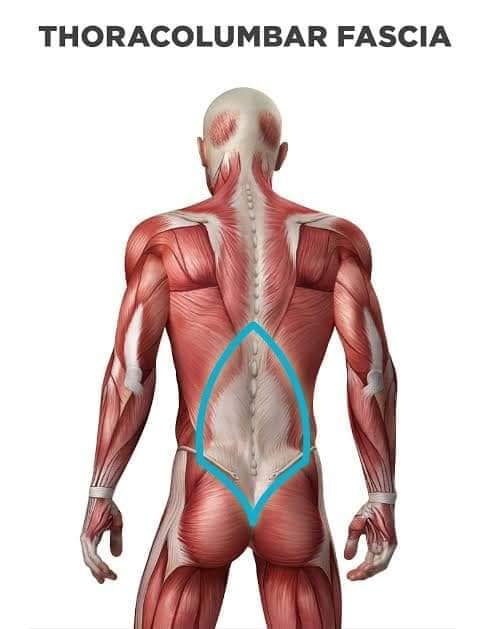

Глибинні спинні м'язи

М'язи, що забезпечують стабільність хребта: М'язи, що розташовані між хребцями: включають мускулатуру, яка забезпечує стабільність і підтримку хребта, а також дозволяє здійснювати рухи хребта.